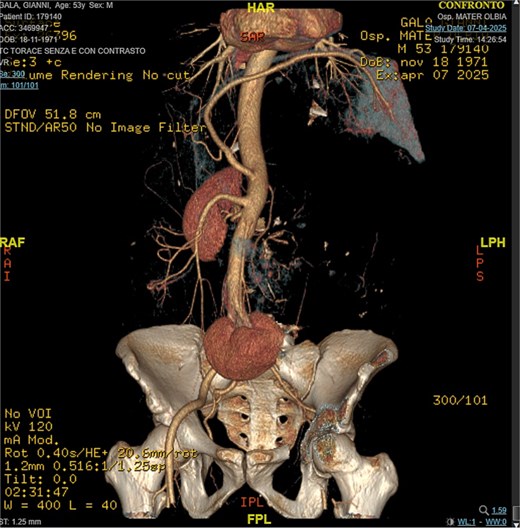

A 53-year-old man, ex-smoker and occasional alcohol consumer, reported several months of postprandial dyspepsia and increased bowel movements (3–4 per day), without weight loss or systemic symptoms. Physical examination revealed a distended, somewhat tense abdomen without focal tenderness. Laboratory tests, including complete blood count, biochemistry, and inflammatory markers, were within normal limits. Cross-sectional imaging demonstrated a multilobulated, predominantly solid retroperitoneal mass measuring 35 × 32 × 18 cm. Contrast-enhanced computed tomography (CT) and magnetic resonance imaging (MRI) showed displacement—but no frank invasion—of the inferior vena cava and aorta, encasement of mesenteric vessels, and compression of bowel loops. A notable anatomic variant was an ectopic left kidney located in the right paramedian pelvis. No distant lesions were identified (Figs 1 and 2). Three-dimensional CT angiography delineated the relationship with major vessels and aided operative planning (Fig. 3). After multidisciplinary discussion, primary surgical resection was favored given the well-circumscribed nature of the mass, the absence of metastatic disease, and the patient’s symptoms. Through a midline xipho-pubic laparotomy, a well-encapsulated, firm, tan-white mass occupying most of the retroperitoneal cavity was exposed. Sharp and blunt dissection allowed complete en bloc excision without capsular violation. Estimated blood loss was modest and no vascular reconstruction was required. Grossly, the specimen weighed approximately 12 kg and showed multinodular architecture with focal myxoid areas.